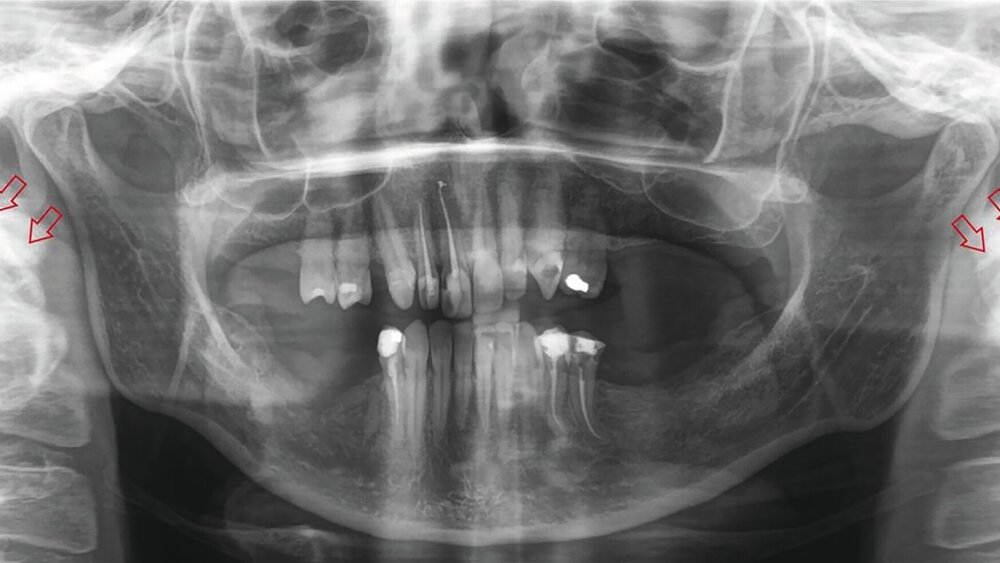

Die bildgebende Untersuchung mittels Orthopantomografie (Abbildung 1) und nachfolgender digitaler Volumentomografie (Abbildung 2) ergab eine Verlängerung des Processus styloideus beidseits, die auch im Rahmen einer dreidimensionalen Rekonstruktion dargestellt werden konnte (Abbildung 3). In Zusammenschau mit der beschriebenen Beschwerdesymptomatik wurde die Diagnose eines Eagle-Syndroms gestellt.

Ausschlaggebend für die Diagnose gilt in der Bildgebung eine Länge des Processus styloideus von über 25 mm und/oder eine ebenso lange Verkalkung des Ligamentum stylohyoideum [Searle und Searle, 2021]. Die Differenzialdiagnosen sind zahlreich, unter anderem Migräne, Clusterkopfschmerz, atypischer Gesichtsschmerz, Craniomandibuläre Dysfunktion, Trigeminusneuralgie, Mastitis, Tonsillitis und Otitis [Montalbetti et al., 1995; Piagkou et al., 2009].